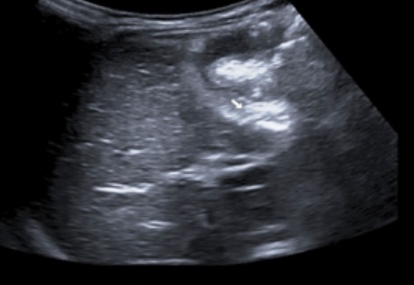

Primary ovarian ectopic pregnancy

Primary ovarian ectopic pregnancy is one of the rarest forms of ectopic pregnancy. Its incidence after natural conception ranges from one in 2,000 to one in 60,000 deliveries and accounts for 3% of all ectopic pregnancies.1 It is estimated that ovarian pregnancy occurs in one in 25,000-40,000 pregnancies.2 It...